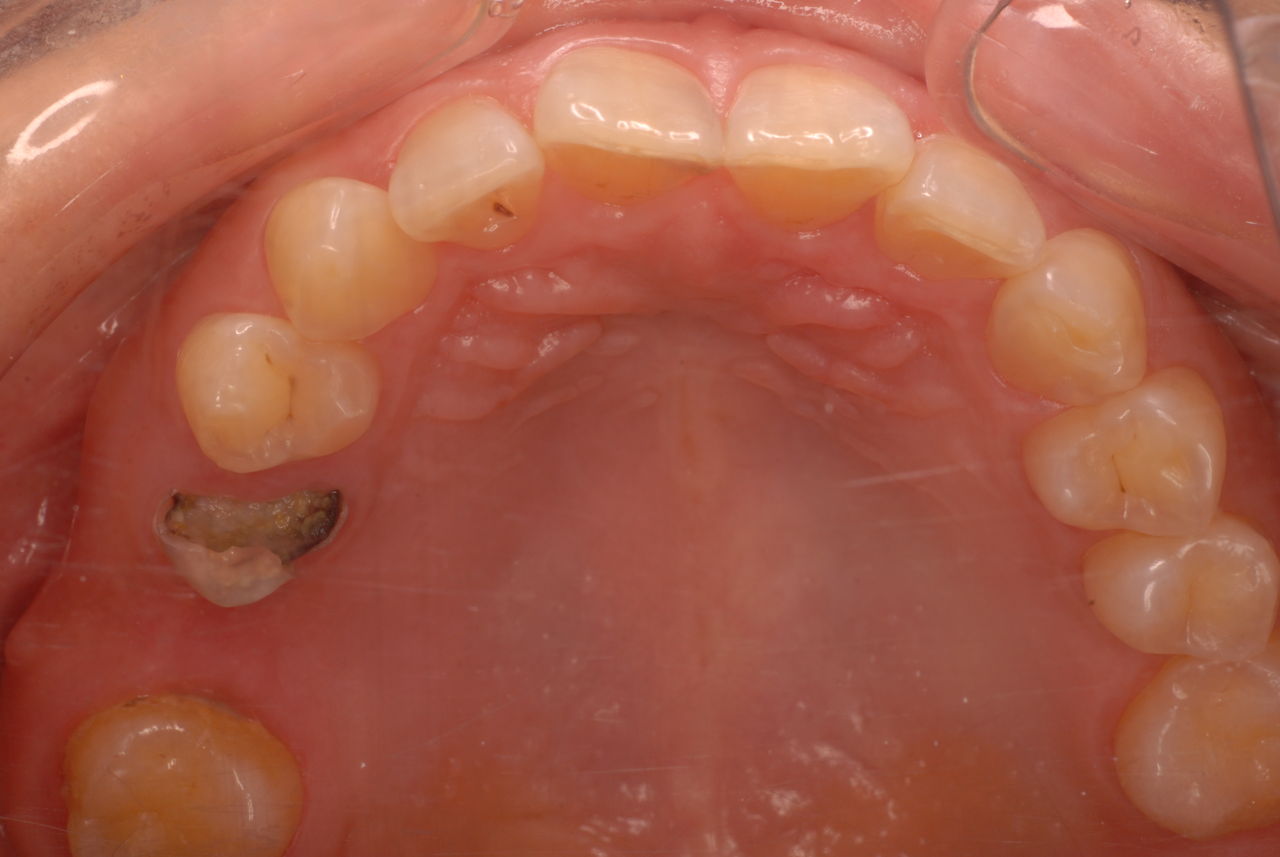

今日のすべての患者さんは、一人を除いて新患を含めてすべて歯周病の方でした。

歯周病は殆どの方に存在し、気づかないうちに進行していきます。

そして場所や痛みなどの症状がはっきりしないのです。冷たい水がしみることもあります。

なかなかブラシの使い方ができていないようで、歯磨きと歯周病でのブラシの使い方は別なのですが、習ったことも検査もされずに金属を被せたりしているようで、これからも歯医者さんで抜かれたり、その後にインプラントのような高価な“クギ”を打ち込まれる方が増えるかと思うと残念です。

まず検査をして、ブラシの使い方を習得して歯医者さんで削ったり抜かれたりしないように予防に注意する方々が増えないかと思う日々です。

被せても、詰めても病気は治らないのですから。又病気の元になり易い不適合な差し歯や金属、インプラントがあればそこからバイキンが侵入して体に悪さもしやすいのではないかと心配しています。